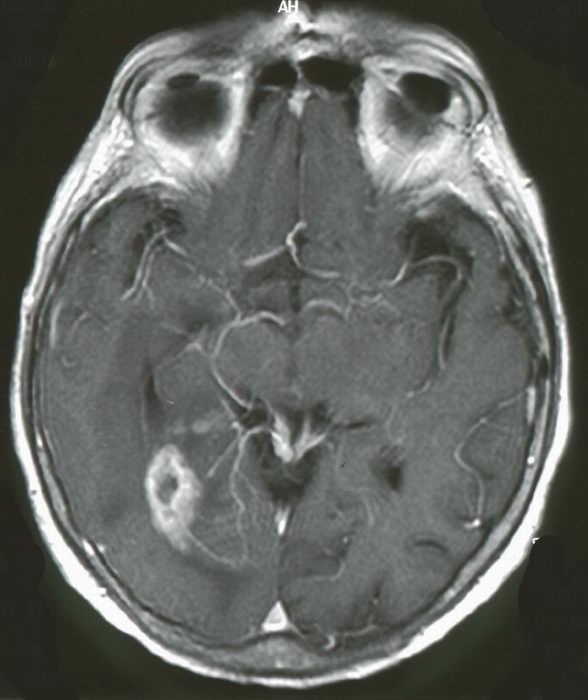

| Epidemiologie | Krebs-Risiko | Tumor - Statistik | ![]() MRT eines Patienten mit Glioblastom im linken Okzipitallappen. Nach Gadolinium - Gabe starke Anreicherung im Tumorgewebe. Darstellung von Tumorgefäßen. |